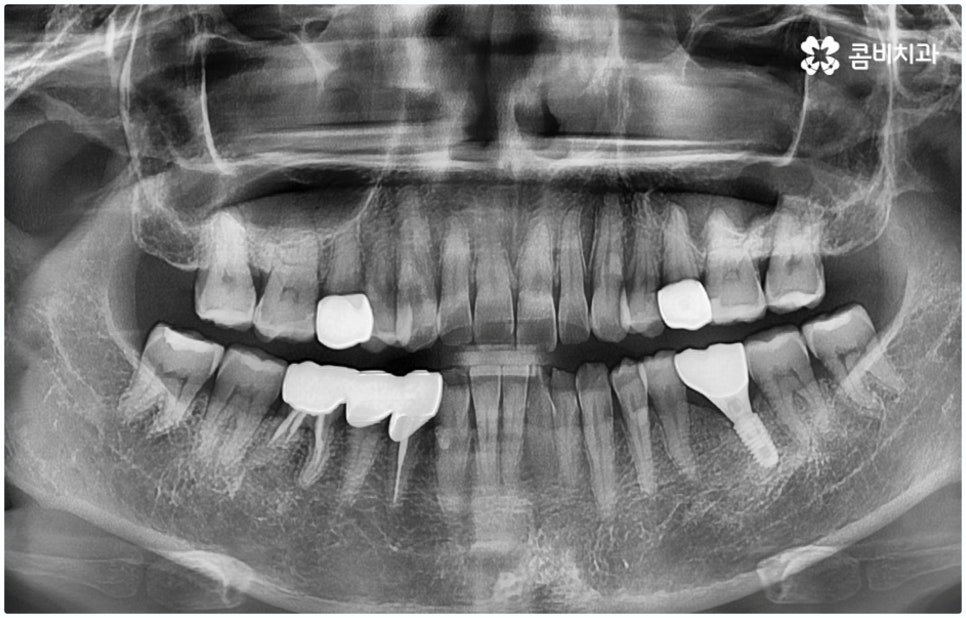

임플란트 시술은 사람의 잇몸뼈와 잘 붙고 인체에 무해한 인공치근(픽스처)을 식립한 후 중간 연결 부분인 지대주와 치아 머리 부분인 크라운을 차례대로 연결하여 기능상 심미상으로 자연 치아를 대체해 주는 인공 치아 식립 방법으로 보통 픽스처를 심을 때 잇몸뼈와 제대로 유착되는 시간이 필요하기 때문에 중간에 일정 시간 회복기를 두고 진행하게 되어 있어요.

이때 환자분들의 상황에 따라 잇몸뼈가 충분하지 않다면 먼저 뼈이식을 통해 이를 단단하게 보충해 주기도 하고, 치주 질환의 치료가 필요하거나 상악동과의 거리가 너무 짧아 거상술이 필요한 경우 이를 선행하기도 하기 때문에 전체 기간은 개개인에 따라 달라질 수 있으며 특히 구강 상태나 연령에 따라 충분한 회복 및 적응 시간을 두지 않으면 식립 성공률이나 장기적인 지속성에 좋지 않은 영향을 줄 수 있으니 주의할 필요가 있습니다.

그렇기 때문에 무조건 보다 빠르고 간편하다고 해서 원데이임플란트 방법을 고집하기 보다는 개인 상태에 따라 필요한 과정을 세심하게 맞춤 진행할 수 있도록 경험이 풍부하고 노하우가 뛰어난 의료진에게 치료 받는 것이 중요한 거예요. 즉 3D CT 등 정밀 검진 장비를 이용하여 환자분들의 치아 및 잇몸 상태, 치아 배열과 교합상태, 주변 치아와의 관계 및 조화까지 꼼꼼하게 파악할 뿐 아니라 턱뼈, 혈관, 신경 등 구강 전체를 함께 분석한 후 체계적인 시술 계획을 세워 각자에 맞는 방법으로 무리하지 않게 수술을 진행할 수 있는 숙련된 의료진과 함께 하는 것이 무엇보다 중요하다고 할 수 있습니다.

또한 잇몸 염증이 없고 치아를 상실한지 오랜 시간이 지나지 않아 남아있는 잇몸뼈가 충분한 분들의 경우와 같이 꼼꼼한 진단 이후 원데이임플란트 수술을 받은 경우라고 해도 사후에 꾸준히 관리해 주지 않으면 임플란트 보철 탈락 및 주위염과 같은 부작용이 생길 수 있으므로 임플란트 수명을 높이기 위해서 치과에서 알려드리는 주의사항을 잘 지키실 필요가 있어요. 또 너무 딱딱하거나 질긴 음식은 피하시고 주기적인 스케일링 치료 및 정기 점검을 받아서 유지 관리에 유념하실 필요가 있습니다